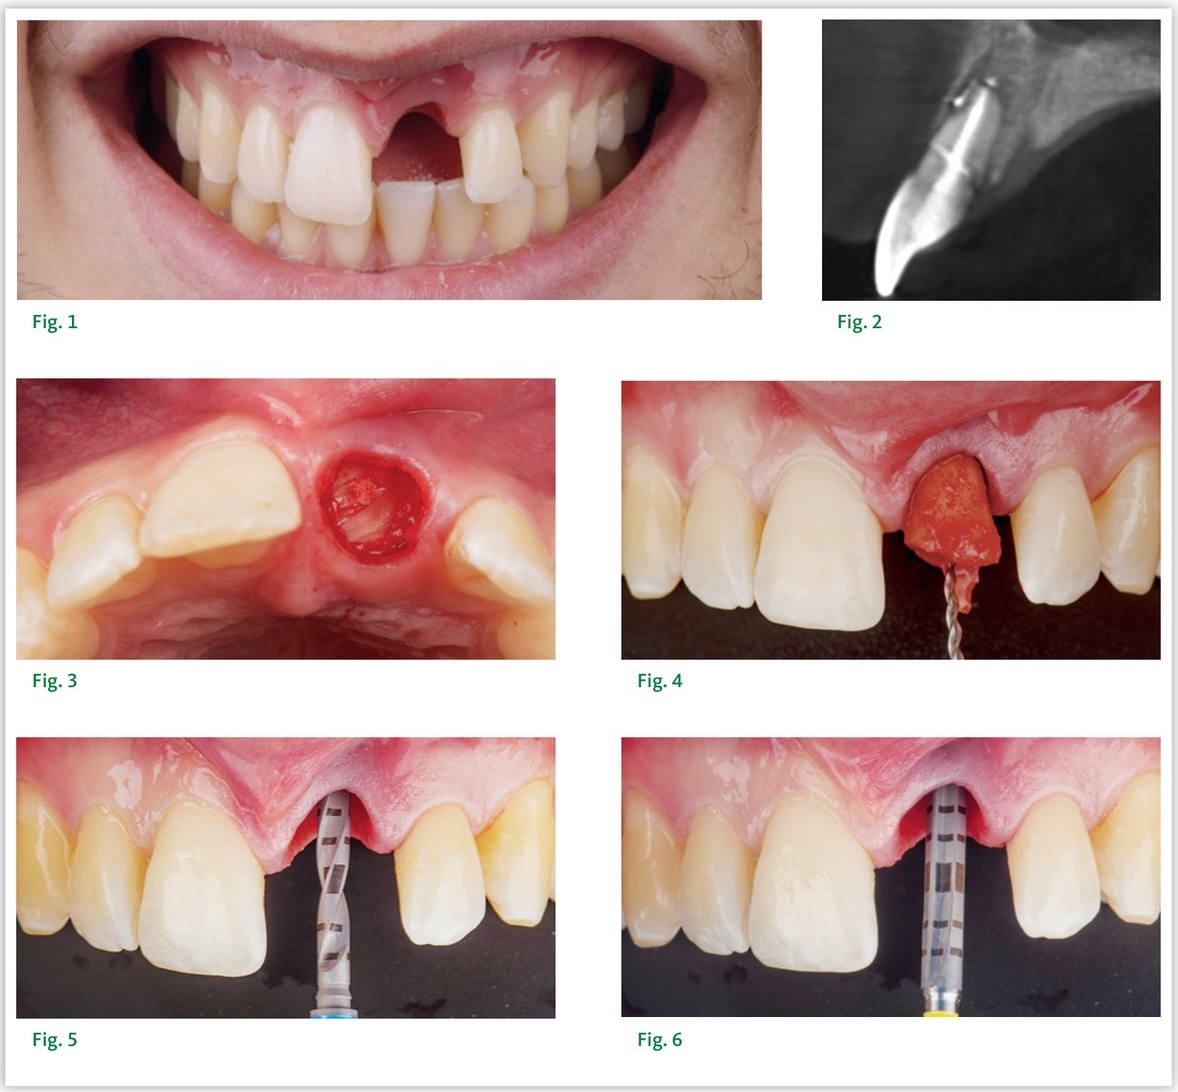

Un patient âgé de 28 ans, en bon état de santé général, se présente en consultation d'urgence ayant fracturé son incisive centrale maxillaire gauche. Le diagnostic comprend une fracture radiculaire et une nécrose. L'examen clinique et radiographique a mis en évidence l'impossibilité de conserver cette dent et l'indication d'extraction a été posée.

Les différentes possibilités de traitement ont été évaluées et discutées avec le patient. Il a été décidé de remplacer la racine de cette dent par un implant. La possibilité de réaliser cette procédure le jour de l'extraction et d'y adjoindre la mise en place d'une couronne provisoire a été déterminée cliniquement. La situation était favorable : classe 1 d'Elian (présence de la corticale osseuse vestibulaire, collet gingival et papilles en situation idéales), classe I de Kan radiographiquement, et volume osseux apical suffisant.

Pour optimiser la mise en place de l'implant, une planification implantaire et un guide chirurgical ont été réalisés de façon systématique. Le modèle d'étude et le wax-up ont été scannés et couplés aux données du scanner dentaire. L'implant a été placé par ordinateur dans sa position tridimensionnelle idéale — un Bone Level Tapered 4,1 × 12 mm — et la planification a été envoyée pour la fabrication d'un guide chirurgical par stéréolithographie.

Après anesthésie locale, la dent est extraite de manière atraumatique sans élever de lambeau ni réaliser d'ostéotomie. Le site est nettoyé mécaniquement puis rincé. La séquence de forage est simple, incluant les forets de 2,2 mm, 2,8 mm et 3,5 mm. L'implant est ensuite inséré et positionné à la profondeur désirée (3 à 4 mm plus profond que le collet gingival idéal). La stabilité primaire mesurée a été de 45 N.cm.